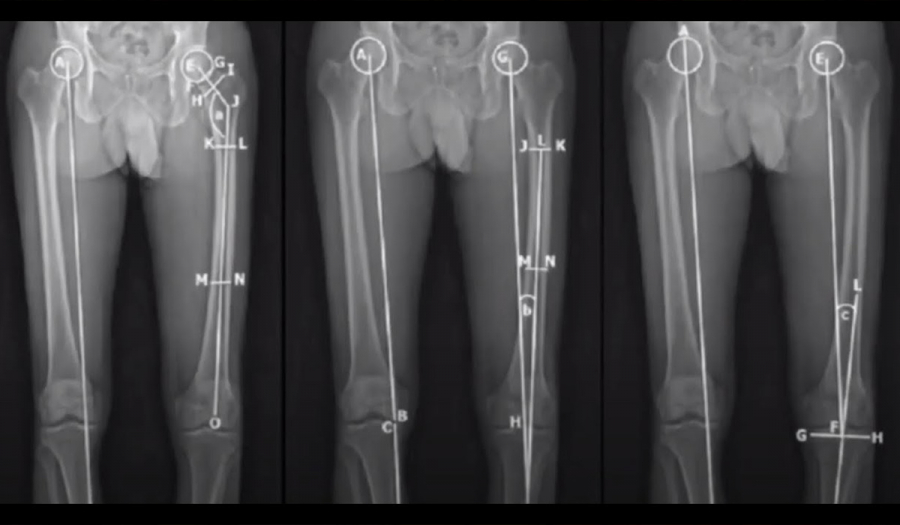

Одним з важливих аспектів сучасної ортопедичної хірургії є подовження і корекція осі нижніх кінцівок.

Це хірургічні втручання, спрямовані на виправлення або зміну довжини та положення кісток у стопі та гомілці. Даний метод є надзвичайно важливим в лікуванні вроджених чи набутих вад структури нижніх кінцівок, які можуть впливати на здоров'я та функціональність опорно-рухового апарату.